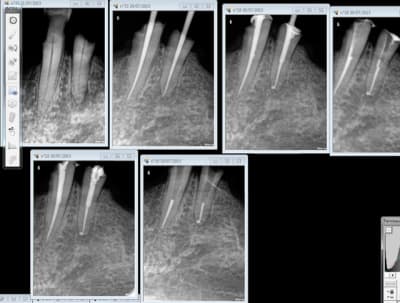

1 .Essayage cones en place, couper ce qui dépasse le cas échéant ( une sur instrumentation ca arrive)

2. scellement des cones.

3. couper les cones au friendo puis phase de descente au friendo ( qui est un heater plugger je le rappelle) et compactage au machtou.

4. coincer les chutes de gutta à l' entrée des canaux et les thermo-compacter au mac spadden.

C'est pret ! -))))

C'est la meme.

J'ai utilisé le peak universal bond ( coltène) seul ( sans etching en plus !) puis estelite flow quick pour la base et estelite posterior pour monter les parois. C'est le collage qui cède pas le compo tu fais ca avec un SAM 1 ca pète, pour te donner le niveau d'adhésion de ces merdes. -)))

Ca c'est pas mal non plus en 45 mn, on se demande pourquoi thermo compacer au mac spadden et j'ai perdu un morceau de crochet au passage ! -)))))